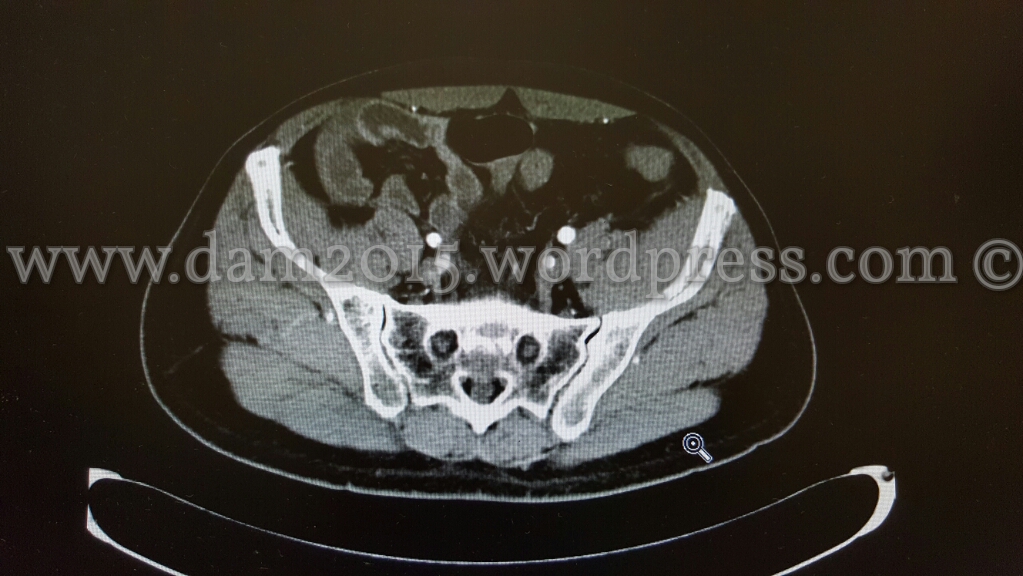

Eseguita TC addome che mostra ispessimento di alcune anse ideali in sede meso-ipogastrica ed in fossa iliaca destra come per infarcimento ematico.

Dopo MDC si osserva iperemia della mucosa a livello delle anse descritte e ridotta rappresentazione della vascolarizzazione del relativo mesentere, che presenta segni di imbibizione edemigena.

I reperti descritti sono suggestivi per quadro di infarto venoso intestinale.